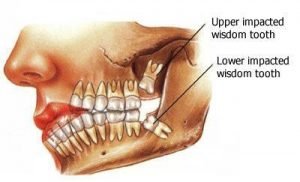

The cost of removing wisdom teeth takes several factors into consideration including the stage of development of the tooth, its position, and the degree of impaction (soft tissue impaction, partial bony impaction and full impaction).

Soft Tissue Impaction

When wisdom teeth that are surrounded by soft gum tissue.

Partial Hard Tissue Impaction

This means that at least part of the top or “coronal” portion of the tooth lies within the jawbone. The complexity of this work will mean that the costs of removal are higher.

Complete Impaction

A full-bony impaction, also called a complete impaction, is where the wisdom tooth is entirely encased by bone tissue. Wisdom teeth that are full impacted require a complex extraction. In most cases the tooth is divided in to multiple parts to make the extraction less traumatic.